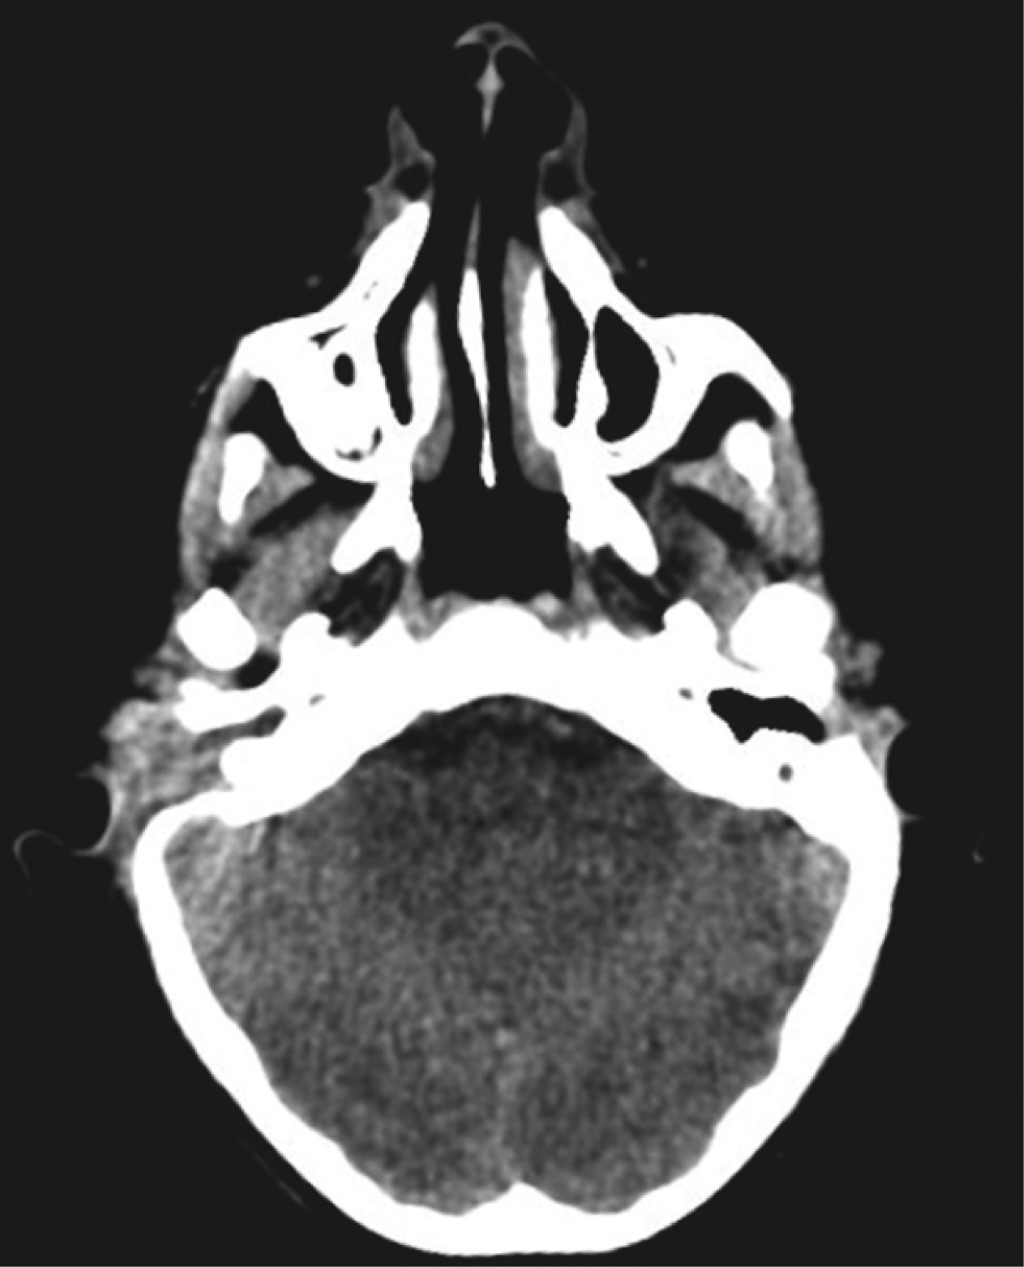

Temporoparietal fascial flap for radical mastoidectomy defect obliteration in a pediatric patient in a national reference center

Rivas-Jiménez J, Mejía-Solís EA, Rojas-Gutiérrez CD, Haro-Cruz JS, Tejada-Aldazosa JE

temporoparietal fascia flap, radical mastoidectomy, pediatric craniofacial reconstruction.

The temporoparietal fascia flap is one of the most versatile flaps for reconstruction of complex head and neck defects; even though its description in cases of mastoidectomy in the pediatric population and its outcomes are not reported in the literature. We present the case of a 10-year-old patient with chronic otitis media who underwent radical mastoidectomy with subsequent reconstruction by temporoparietal fascia flap with a good result. The temporoparietal fascia flap is a flap that can be used in cases of osteomyelitis in the temporal region offering an appropriate coverage of the region with minimal donor site morbidity and favorable results.

Figure 1

Figure 2

Figure 3

Figure 4

Figure 5

Figure 6